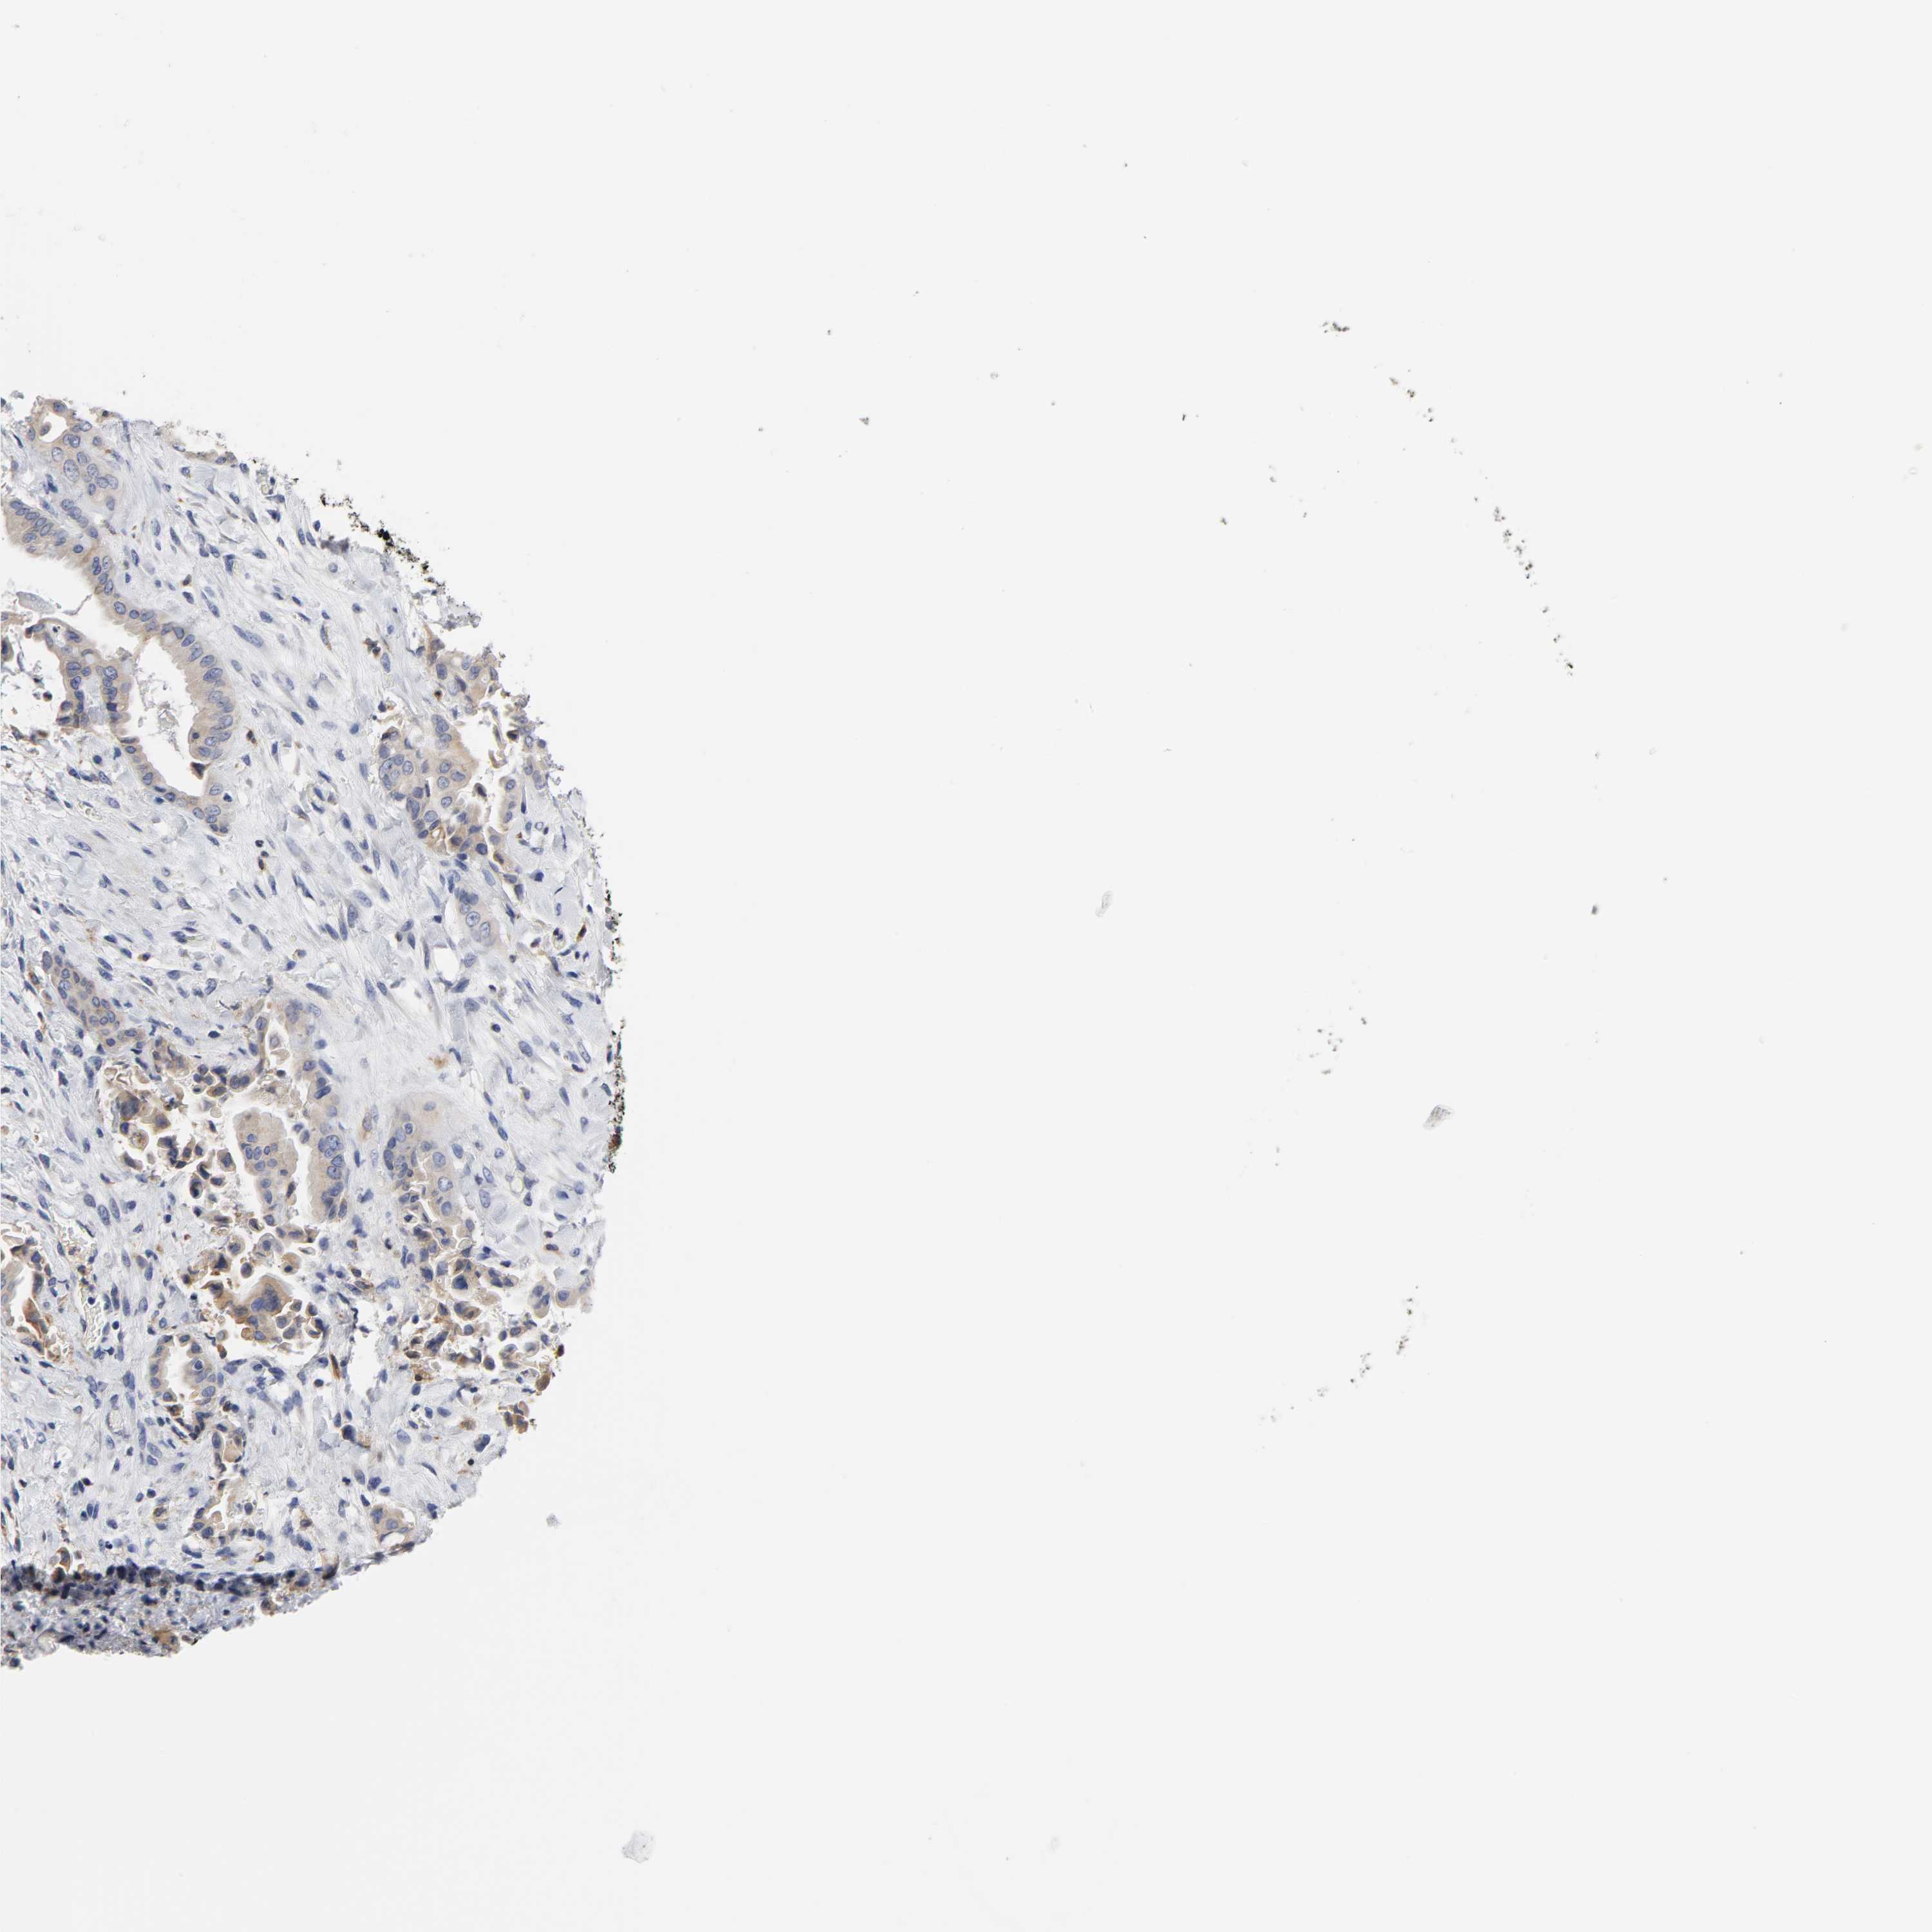

LIVER CANCER - Protein expressioni

A mouse-over function shows sample information and annotation data. Click on an image to view it in a full screen mode. Samples can be filtered based on level of antibody staining by selecting one or several of the following categories: high, medium, low and not detected. The assay and annotation is described here.

Antibody stainingi

Antibody staining in the annotated cell types in the current human tissue is reported as not detected, low, medium, or high, based on conventional immunohistochemistry profiling in selected tissues. This score is based on the combination of the staining intensity and fraction of stained cells.

Each image is clickable and will lead to virtual microscopy that enables deeper exploration of all samples and also displays staining intensity scores, fraction scores and subcellular localization as well as patient and tissue information for each sample.

Antibody CAB005195

Cholangiocarcinoma

Carcinoma, Hepatocellular, NOS